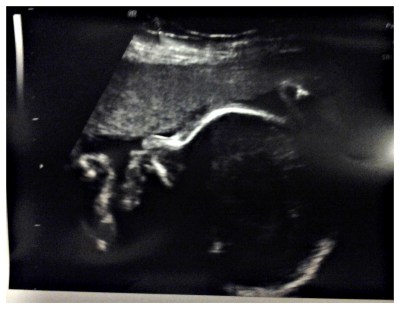

L’altroieri abbiamo fatto la nostra quarta ecografia e ormai no, non c’entra piu’ tutta sotto l’ecografo.

L’ecografista sostiene che nascera’ ciccia come lo era il papa’, visto che ora e’ un chilo e venti e si trova al 6° percentile (vabbe’ sesto, mica ottavo, dai…); la ginecologa dice che invece e’ tutto nella norma. Per noi l’importante e’ che stia bene, e che si faccia sentire, e che la placenta, che e’ ancora un po’ troppo bassa, consenta ad entrambe di arrivare bene ad un parto naturale. E se no faremo la C section e saremo felici lo stesso.

Su “the bump” mi dicono melanzana! Sgambetta tantissimo anche il mio ortaggio, i piedini li hai mai sentiti distintamente? Che impressione!!!! La Picci ha un profilo bellissimo! Per rivedere Cecilia devo aspettare il 2 ottobre….. 😉 abbraccio cara